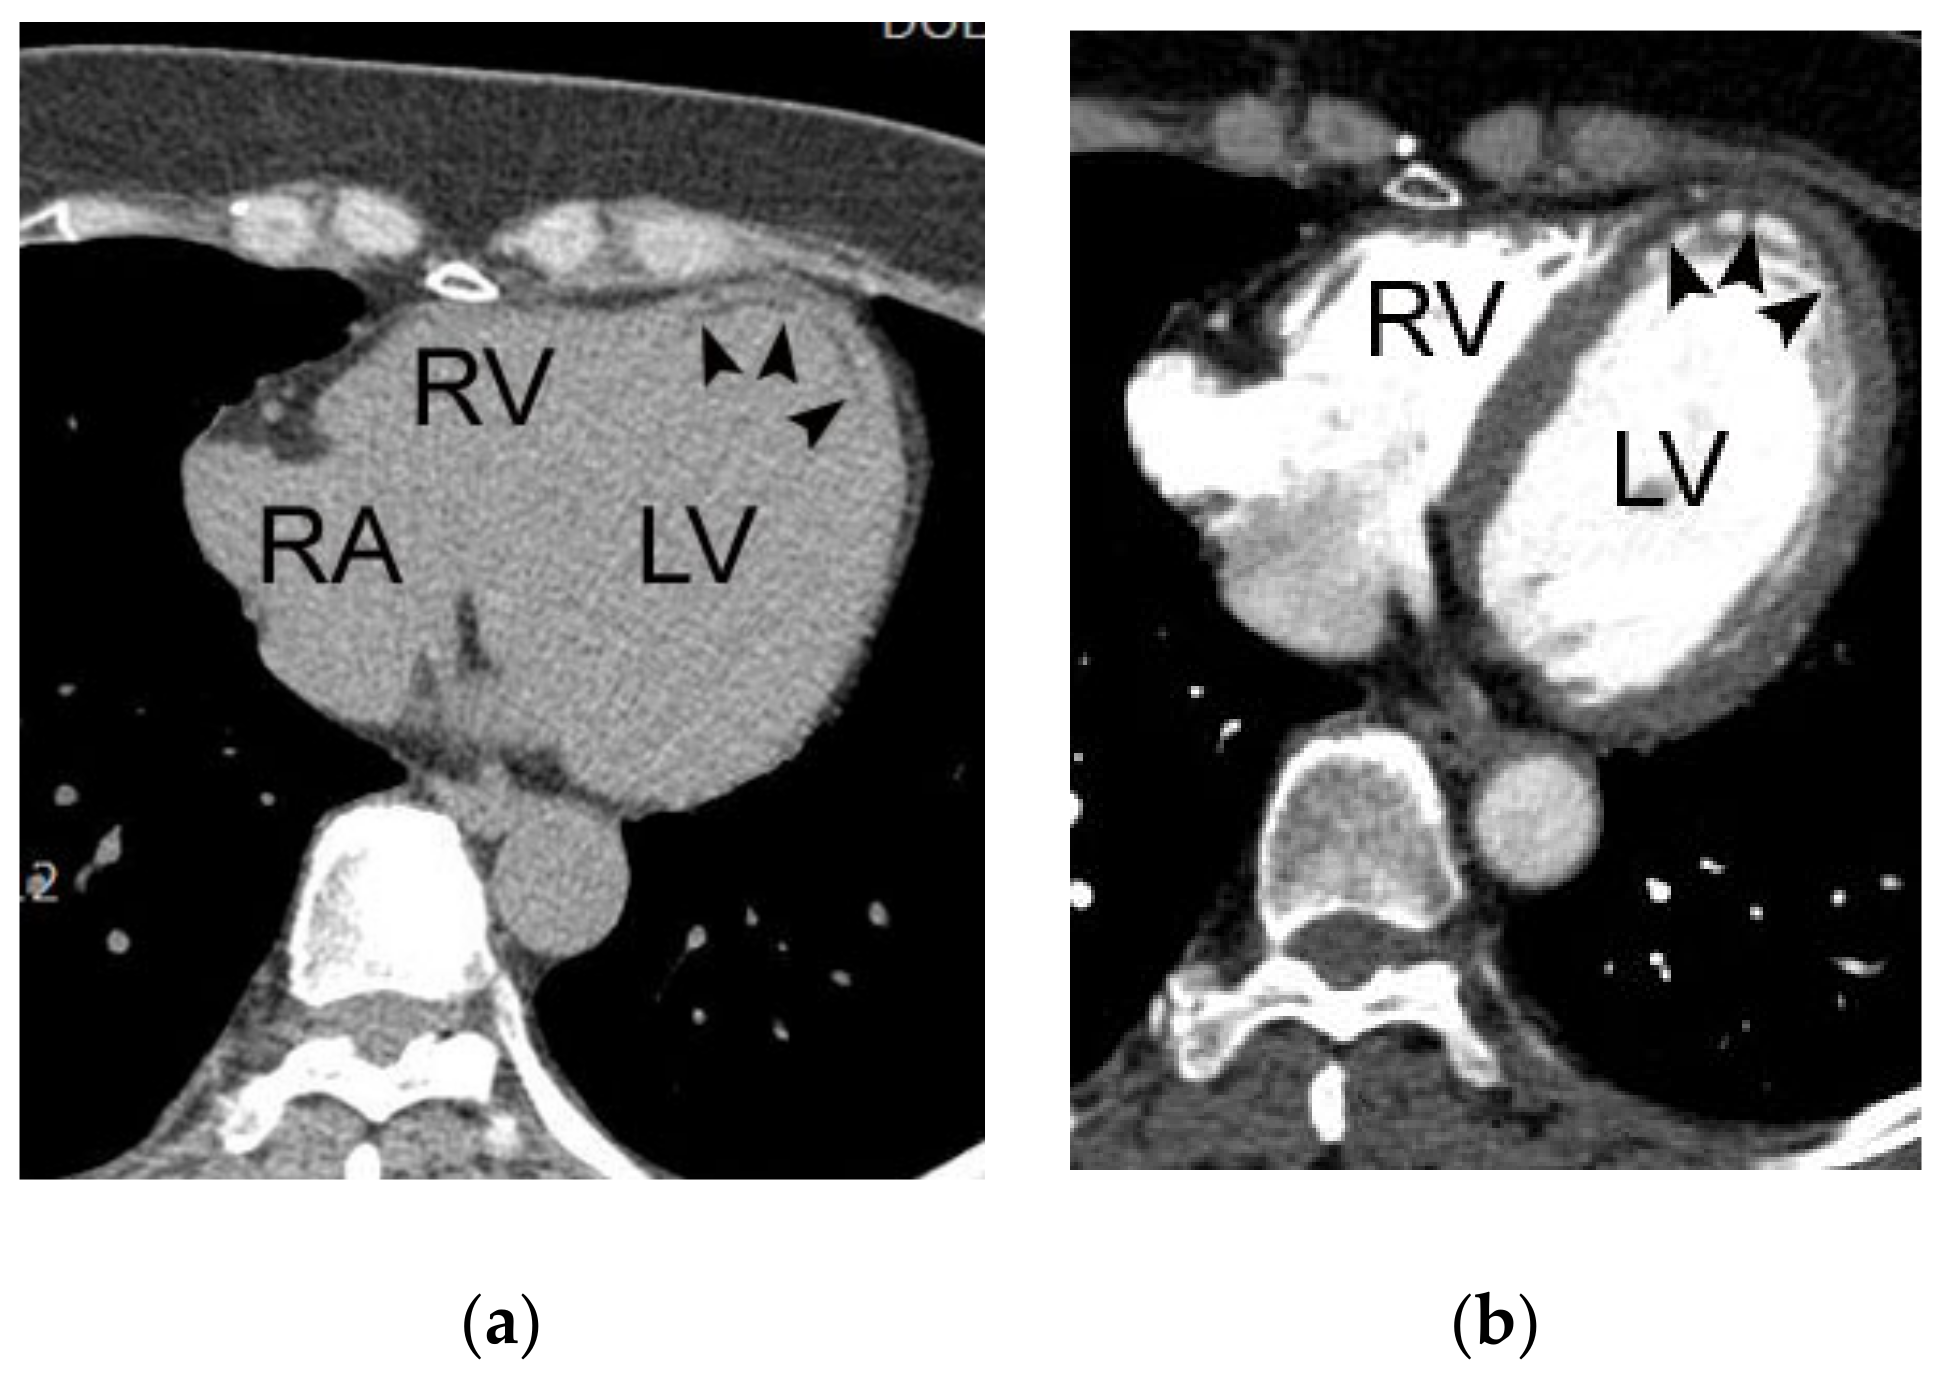

4.4. Myocardial Abnormalities of Acute Coronary Syndrome

4.5. Complications of Acute Myocardial Infarction

- Seneviratne, S.K.; Truong, Q.A.; Bamber, F.; Rogers, I.S.; Shapiro, M.D.; Schlett, C.L.; Chae, C.U.; Cury, R.; Abbara, S.; Brady, T.J.; et al. Incremental diagnostic value of regional left ventricular function over coronary assessment by cardiac computed tomography for the detection of acute coronary syndrome in patients with acute chest pain: From the ROMICAT trial. Circ. Cardiovasc. Imaging 2010, 3, 375–383. [Google Scholar] [CrossRef]

- Mahnken, A.H.; Bruners, P.; Katoh, M.; Wildberger, J.E.; Günther, R.W.; Buecker, A. Dynamic multi-section CT imaging in acute myocardial infarction: Preliminary animal experience. Eur. Radiol. 2006, 16, 746–752. [Google Scholar] [CrossRef] [PubMed]

- Moore, A.; Goerne, H.; Rajiah, P.; Tanabe, Y.; Saboo, S.; Abbara, S. Acute Myocardial Infarct. Radiol. Clin. N. Am. 2019, 57, 45–55. [Google Scholar] [CrossRef]